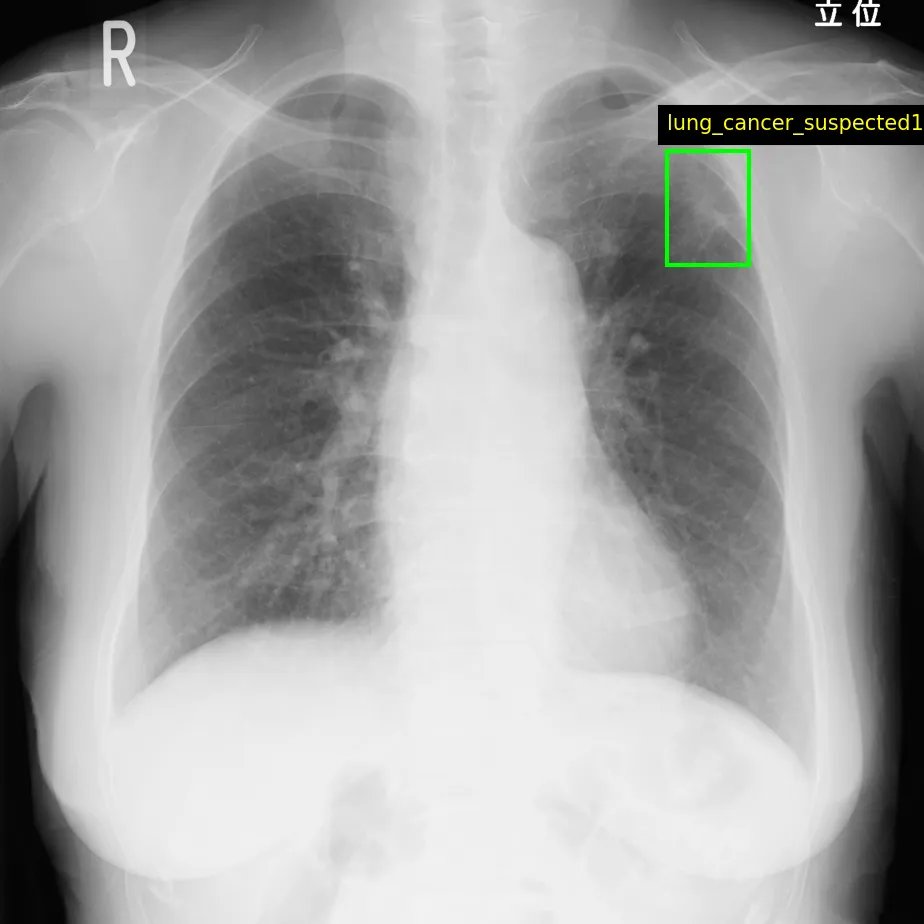

カリスト株式会社が運営する医用画像データプラットフォーム、Callisto DataHubがその2周年を迎えるにあたり、肺がん疑いX線と前立腺がんMRIの正解付きデータセットをそれぞれ50症例ずつ、無料で配布することを発表しました。このデータセットは商用利用も可能で、特に日本の医療機関由来のため、日本国内やアジア人を対象とした研究に最適です。

Callisto DataHubは多様な医用画像データを取り扱っています。具体的には、X線、CT、MRI、PET、超音波画像、病理画像などがあり、それぞれ専門的なアノテーション付きで提供されます。特に、肺がんや前立腺がんを対象としたデータは、多くの研究者や医療機関からの関心を集めています。これにより、診断技術の向上や新たな研究手法の確立を促進します。